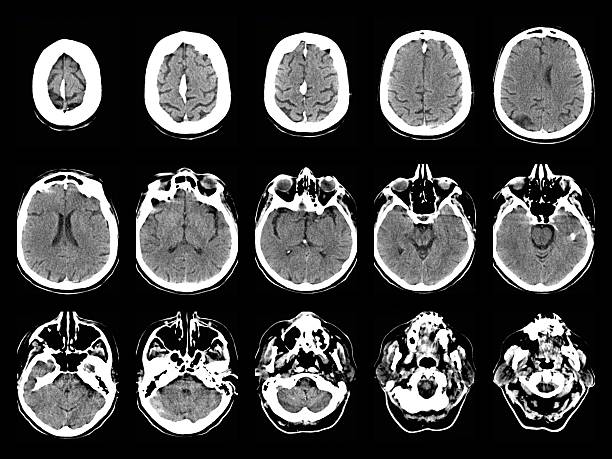

神經(jīng)系統(tǒng)疾病,也稱為神經(jīng)系統(tǒng)疾病或病癥,是影響中樞神經(jīng)系統(tǒng)(大腦和脊髓)、周圍神經(jīng)系統(tǒng)(大腦和脊髓以外的神經(jīng))或兩者的疾病。這些疾病是由神經(jīng)系統(tǒng)的結(jié)構(gòu)、功能或化學(xué)異常或功能障礙引起的。

隨著年齡的增長,神經(jīng)系統(tǒng)問題會(huì)變得越來越普遍。影響老年人的一些最常見的神經(jīng)系統(tǒng)疾病包括: